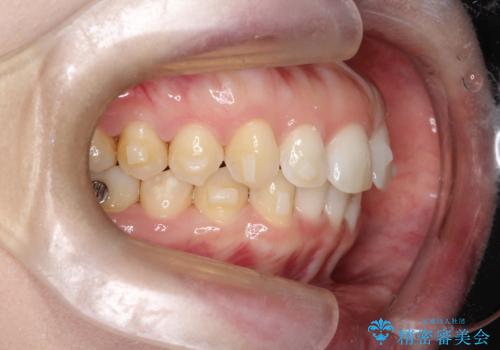

【インビザライン】前歯の凸凹を治したい。

- 前歯の凸凹を主訴に来院されました。

深い噛み合わせも同時に治療を行う計画を立て、インビザラインを使用して歯並びの改善を行うことができました。

叢生改善のために遠心移動とIPRを行なっています。